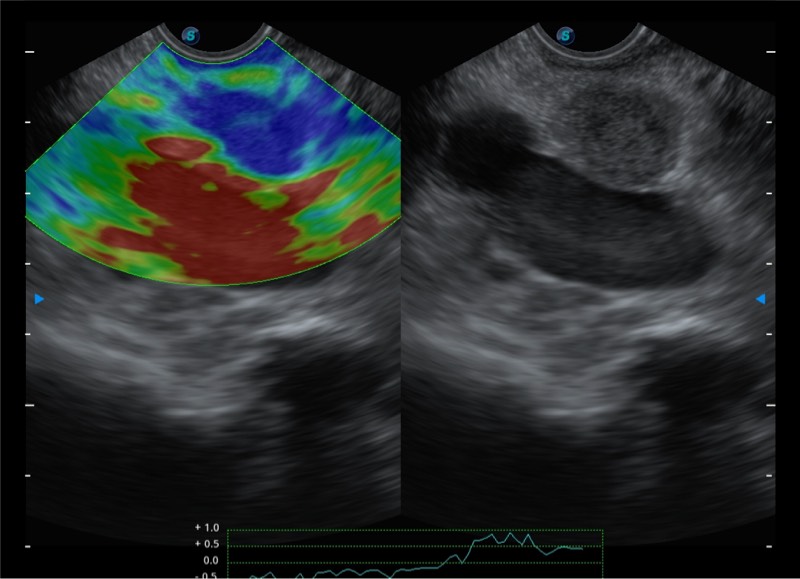

基于二十年的超声技术积累,db真人体育官网提供了最新一代的独立超声主机,在提供高质量图像的同时满足多学科使用。具备常见多普勒技术并提供弹性成像、声学造影等高端影像技术。新一代传感器具有更强的抗干扰能力并减少图像伪影。

• 150°超声扫描角度

• 4-12MHZ宽频输出